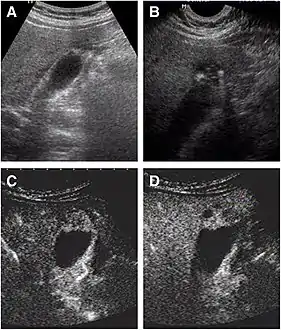

Non-contrast abdominal ultrasound and contrast-enhanced ultrasound (CEUS) of adenomyomatosis of the gallbladder:[8]

a The fundus of the gallbladder wall was thickened and the GB wall was obscure.

b The intramural echogenic foci were detected by high frequency transducer.

c CEUS—arterial phase (22 s) —heterogeneous hyper-enhancement and wall was intact.

d CEUS—venous phase (34 s) the anechoic spaces were more clear.

Abdominal ultrasound has low accuracy in differentiating gall bladder adenomyomatosis from cancer and is operator dependent. However, it is used as the exam of the first-line due to its wide availability. Ultrasound findings may show thickened gall bladder wall, tiny anechoic spaces (Rokitansky–Aschoff sinuses or RAS), and twinkling artifact (or comet-tail reverberation). Comet tail reverberation, which is due to reflections from cholesterol crystals, is a highly specific sign for adenomyomatosis.[9]